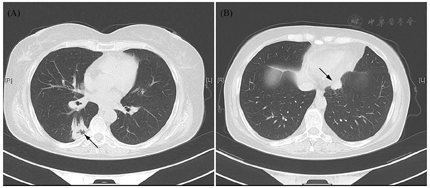

影像学资料:鞍区MRI平扫+增强提示垂体后叶及垂体柄信号异常(图1)。甲状腺超声:甲状腺实质弥漫性病变,不除外桥本甲状腺炎。全身浅表淋巴结超声波检查提示双侧锁骨上区多发稍大淋巴结,右侧大者1.0 cm×0.7 cm,左侧大者0.9 cm×0.7 cm。肺CT:右肺下叶背段空洞合并双肺多发性结节影(图2)——化脓性感染、肺脓肿?经CT引导下右肺下叶结节穿刺活检,病理学检查结果回报:肺间隔明显增宽,部分实变,伴大量淋巴细胞、浆细胞及少许嗜酸性粒细胞浸润(图3)。免疫组化染色提示CD138+、IgG4+,部分热点区域IgG4+细胞约为40个/高倍视野。特殊染色:弹力纤维+,革兰氏-,PSA-,PASM-,黏液卡红-。请结合临床除外IgG4相关性疾病(IgG4-related disease, IgG4-RD)。未见明确真菌、结核及肿瘤性病变。腹部CT未见异常。

治疗上,确诊为IgG4-RD后,予强的松龙40 mg QD口服治疗。针对尿崩症,给予醋酸去氨加压素:早0.1 mg、午0.05 mg、晚0.1 mg,治疗后每日入量约2 000~3 000 ml,尿量2 000~3 000 ml,出入量大致平衡,血钠降至正常。对于糖尿病,予阿卡波糖控制血糖,空腹血糖约5~7 mmol/L,餐后2 h血糖约7~10 mmol/L。对于类风湿性关节炎,给予来氟米特、硫酸羟氯喹治疗。1个月后患者病情稳定出院。出院前复查空腹C肽561.5 pmol/L。甲状腺功能:TT3 0.93 ng/ml、TT4 8.1 μg/dl、FT3 2.28 pg/ml、FT4 0.87 ng/dl、TSH 1.44 mIU/L。皮质醇:08∶00 17.5 μg/dl。ACTH:08∶00 18.3 pg/ml。出院后患者定期随诊,门诊复查HbA1C 6%。出院半年后强的松龙改为强的松。目前醋酸去氨加压素为早0.2 mg、午0.1 mg、晚0.1 mg,强的松5 mg qd,IgG4下降至0.534 g/L,患者病情稳定,复查肺部病变较前缩小(图4)。